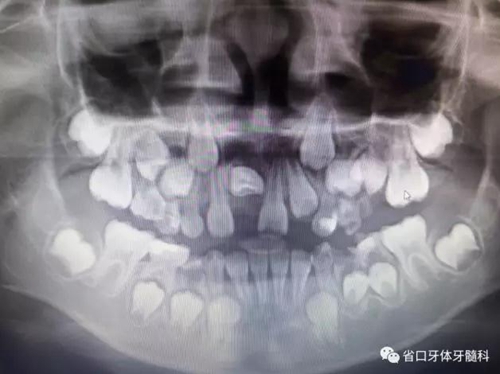

X線檢查:全景片

CBCT顯示右上中切牙埋伏阻生,牙軸呈水平位,冠向唇側(cè)、

根向腭側(cè),與鄰牙成90°夾角,牙根尚未發(fā)育完成,根端輕微彎曲。

診斷:11水平埋伏阻生。